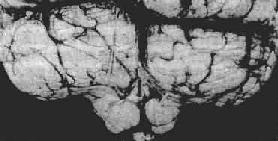

小脑扁桃体疝

图16-8 小脑扁桃体疝

示小脑切迹,两侧扁桃体疝形成